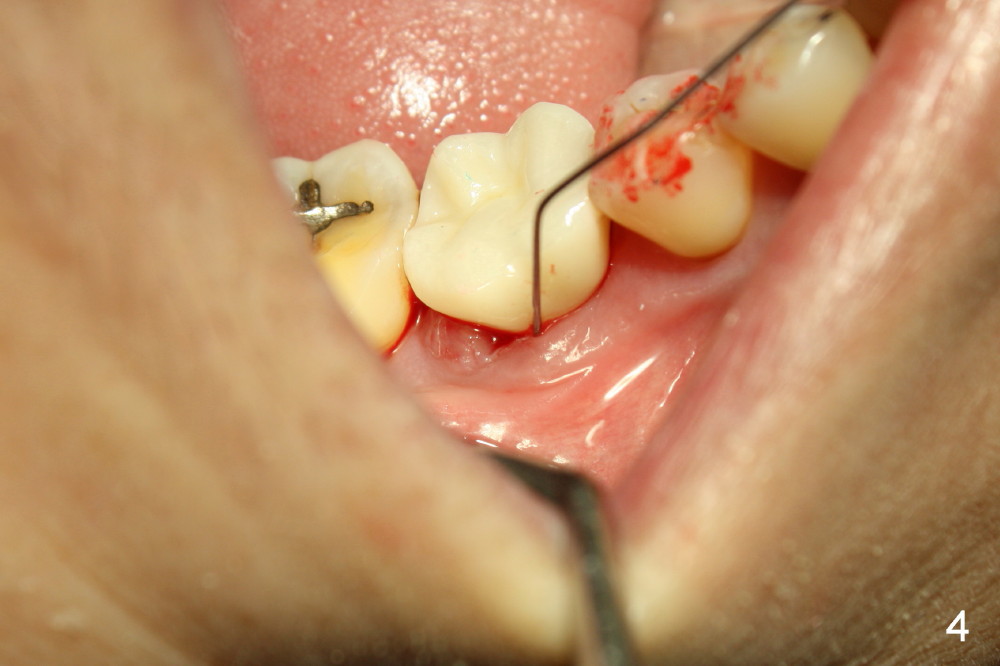

A gingiva-level implant (Fig.1 I) is placed immediately in the extraction site of the tooth #30 (*: remaining mesial and distal sockets after implantation). There appears to be no bone growth in the sockets 4 month postop (Fig.2), although the implant is stable. Clinically there is sign of infection (Fig.3 <) distobuccal to the implant (I). Since the patient is asymptomatic, it feels that the infection may resolve by itself. The abutment (A) is placed and impression is taken. Fourteen days later, the infection remains (Fig.4) after seating the permanent crown.